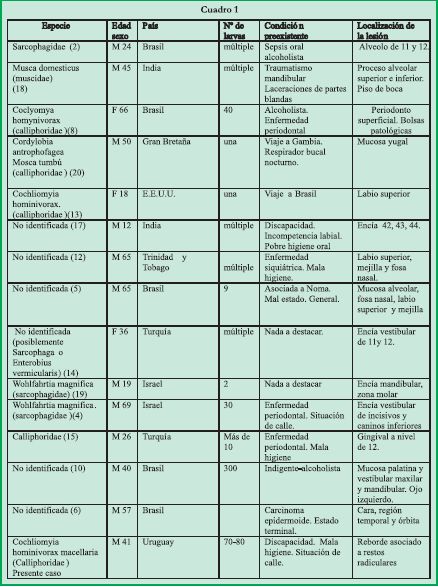

Las especies encontradas en miasis orales se describen en el cuadro 1.

Mundialmente se han reportado casos en Brasil (13), Trinidad y Tobago (12), Turquía (14,15), India (16,17,18), Israel (19) y Gambia (20). En nuestro medio no existen publicaciones al respecto, sólo casos aislados en muchos años por lo que la incidencia y prevalencia de la miasis oral es muy baja.